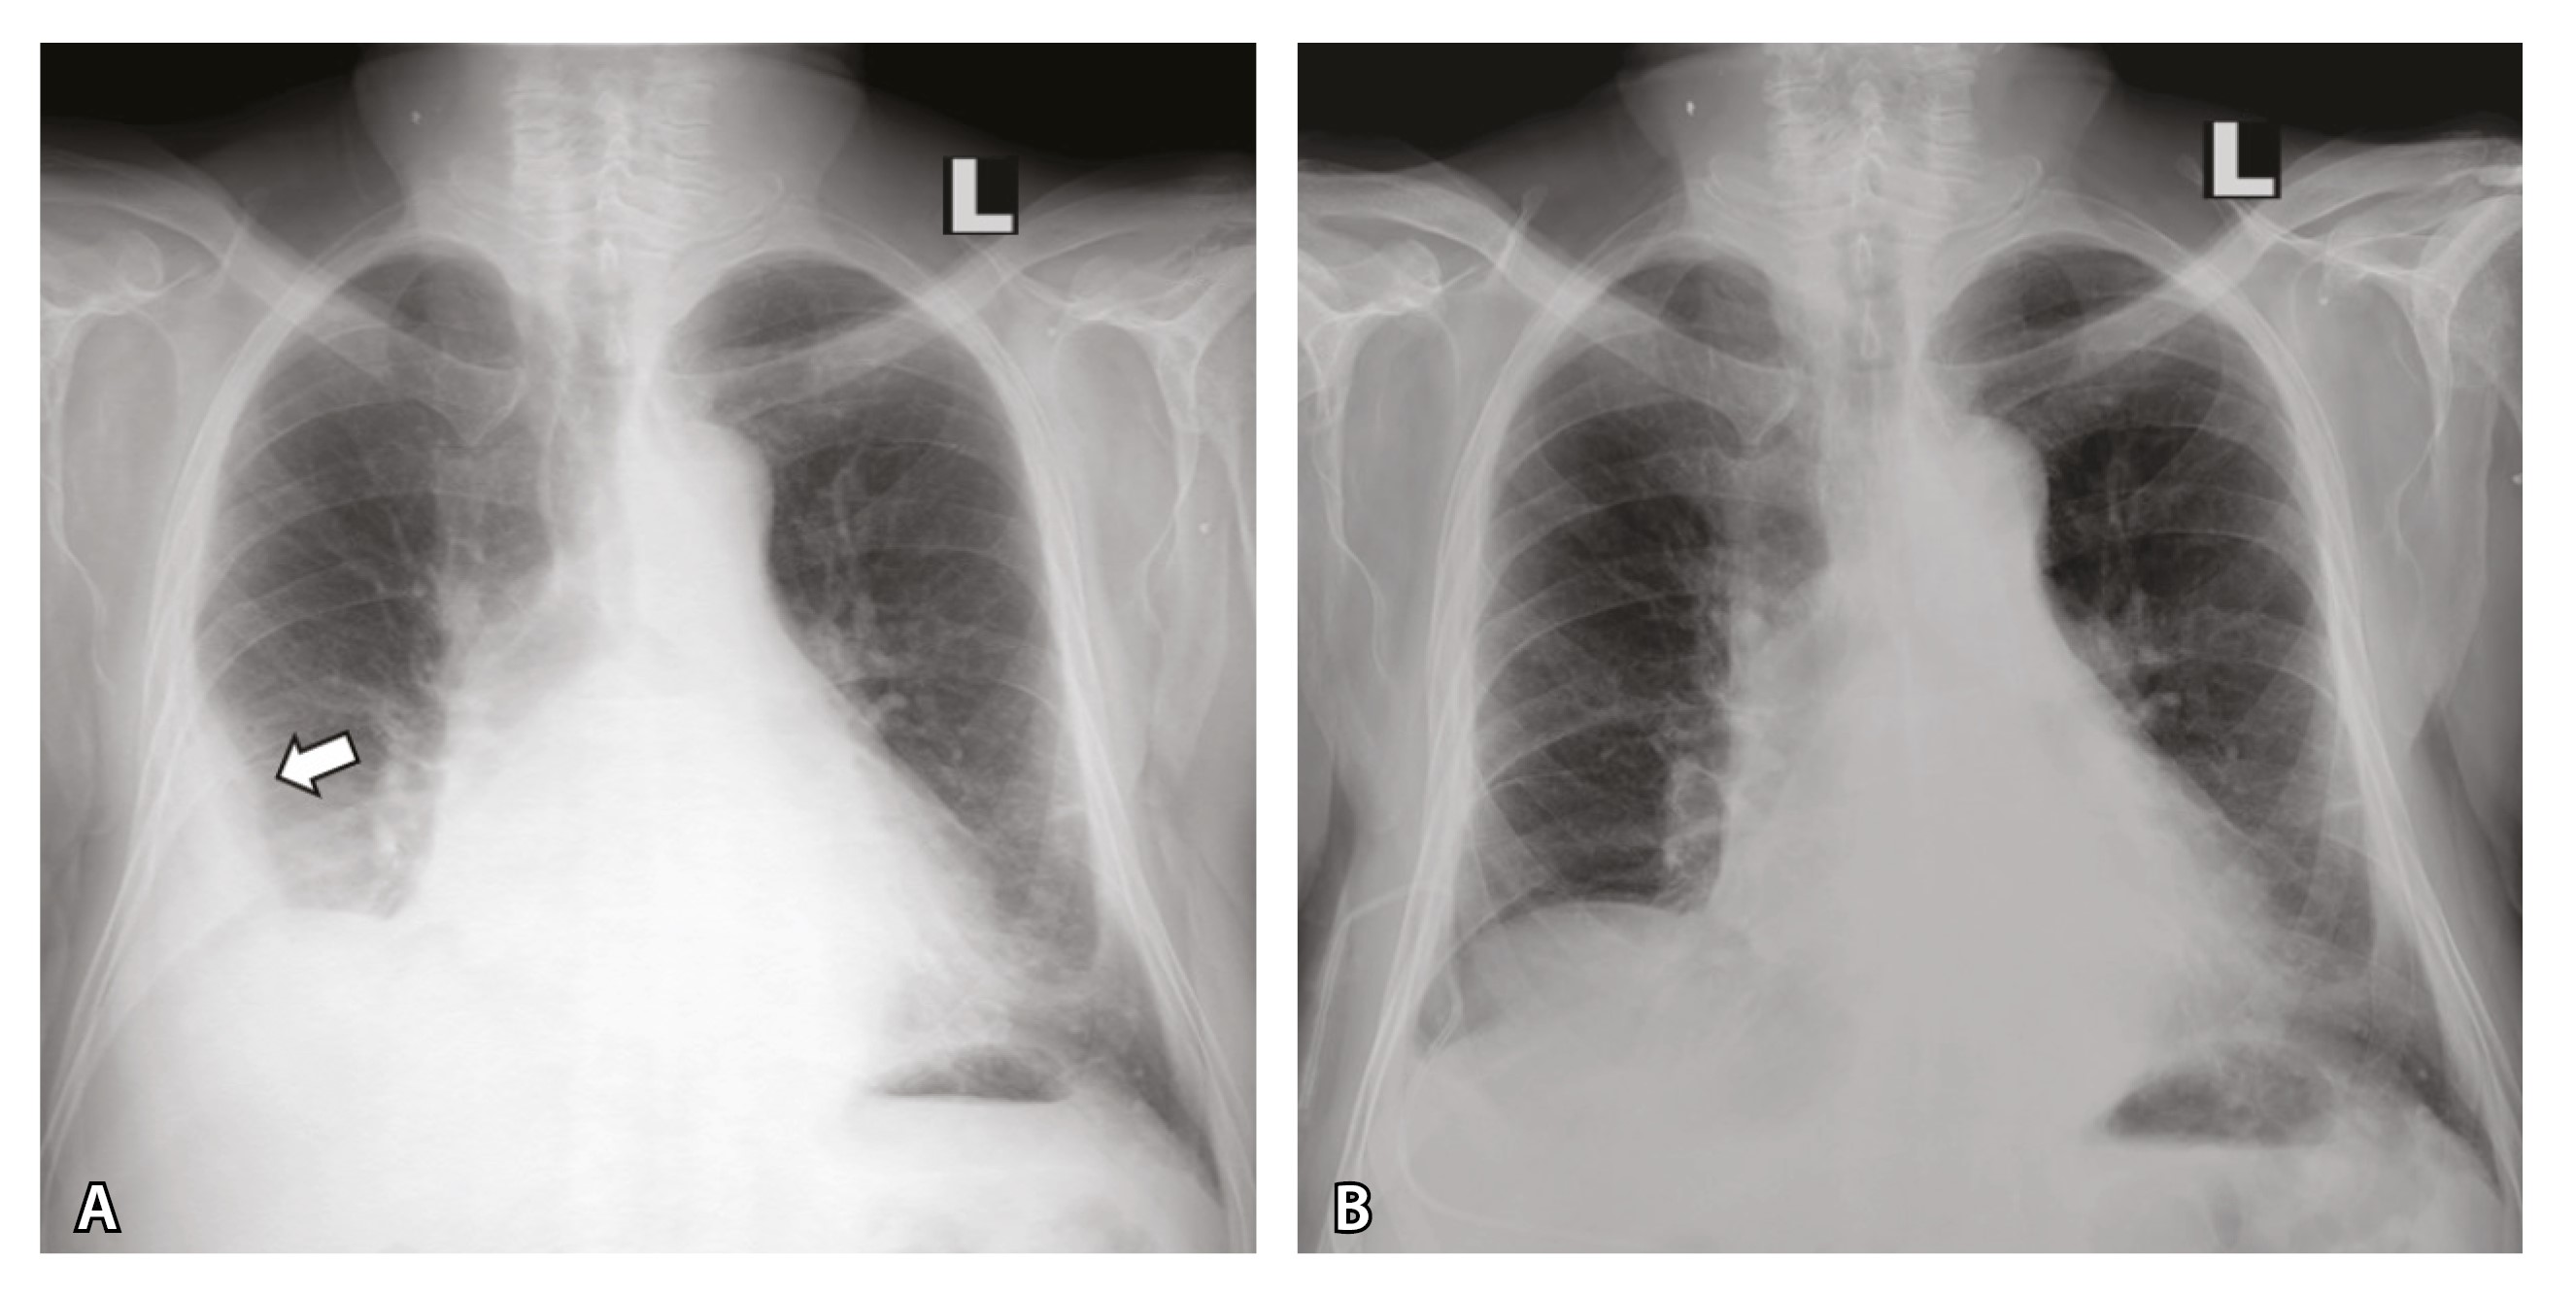

Кроме того, при УЗИ и рентгенографии 19.03.2024 выявлен правосторонний гидроторакс, расширение срединной тени. Проведено дренирование правой плевральной полости (рис. 2), эвакуировано 1700 мл соломенно-желтой жидкости. 20.03.2024 зафиксирован очередной пароксизм ФП (см. рис. 1).

Рис. 2. Рентгенограмма органов грудной клетки пациента до (А) и после (Б) плевральной пункции. Стрелкой указан косой верхний контур уровня жидкости в правой плевральной полости на уровне переднего отрезка 4-го ребра. Синусы слева прослеживаются. Тень сердца расширена